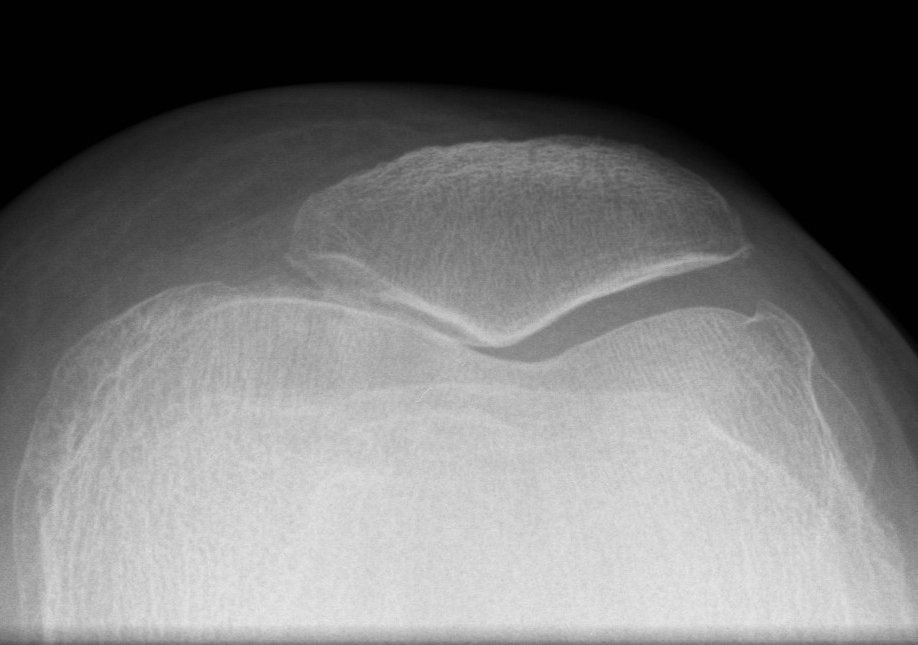

MRI

Moderate lateral facet PJF OA with tilt

Severe lateral PFJ OA in the setting of maltracking / subluxation / tilt